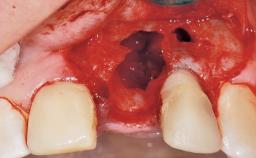

A 29-year-old female patient presented for treatment to replace the upper left central incisor tooth with an implant- supported restoration. The tooth had been intermittently symptomatic for the previous 12 months. The tooth had originally suffered trauma about 15 years previously. Several endodontic treatments had been performed, including an apicectomy procedure to retain the tooth. The patient was healthy and a non-smoker. She had reasonable expectations in regard to esthetic outcomes and the risk of marginal tissue recession following treatment. At medium smile, the gingival margins of the upper teeth were visible, with a display of 3 to 4 mm of the gingival margins. Gingival recession of tooth 21 and a discrepancy in the gingival levels between teeth 11 and 21 was observable during normal speech and smile.

Placement Protocol Immediate implant placement

Tooth Site Maxillary incisor or canine

Socket Morphology Single-root socket

Socket Integrity Damage to one or more bone walls

Bone Volume Damage to one or more socket walls